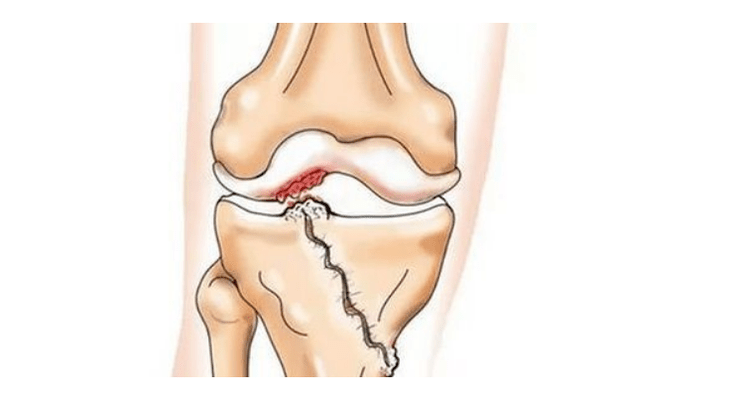

- injuries (fractures, ruptures of the meniscus and anterior cruciate ligament).Unfortunately, in every person, regardless of age, these injuries lead to an excessive load on the cartilage.A fracture of any part of the bones covered with cartilage is accompanied by the formation of a bump - a "step".In this area, during movement, abrasion occurs and arthrosis is formed;

In arthrosis (osteoarthrosis), in addition to the progressive destruction of cartilage, loss of its elasticity and cushioning properties, the bones are gradually involved in the process.Under load, sharp edges (exostoses) appear, which are mistaken for "salt deposits" - in classic arthrosis, salt deposition does not occur.As osteoarthritis progresses, it continues to "eat" the cartilage.Then the bone deforms, cysts form, all joint structures are affected, and the leg bends.

Its cause is usually subluxation, fracture or lateralization of the patella.